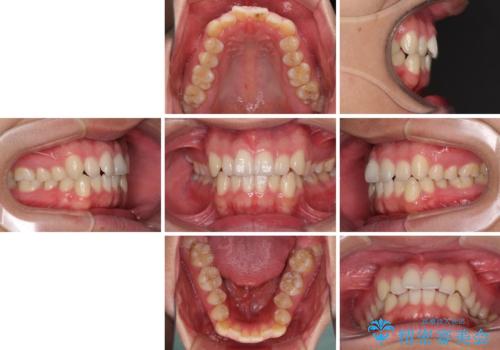

狭い歯列と前歯のデコボコ インビザラインによる矯正治療

- 上下前歯のデコボコを気にして来院された患者様です。

インビザラインによる上下歯列の拡大と、IPR(歯と歯の間を削る)にるスペースの獲得により、前歯のデコボコと狭い歯列を改善することとしました。

比較的軽度な歯列不正であったため、治療期間はそれほど長くはならないと予想されました。

しかしながら、あまりしっかりとマウスピースを装着していなかったため、思いの外期間が長引いてしまいました。

また、仕上がりの歯列にも若干の叢生が残ってしまいました。